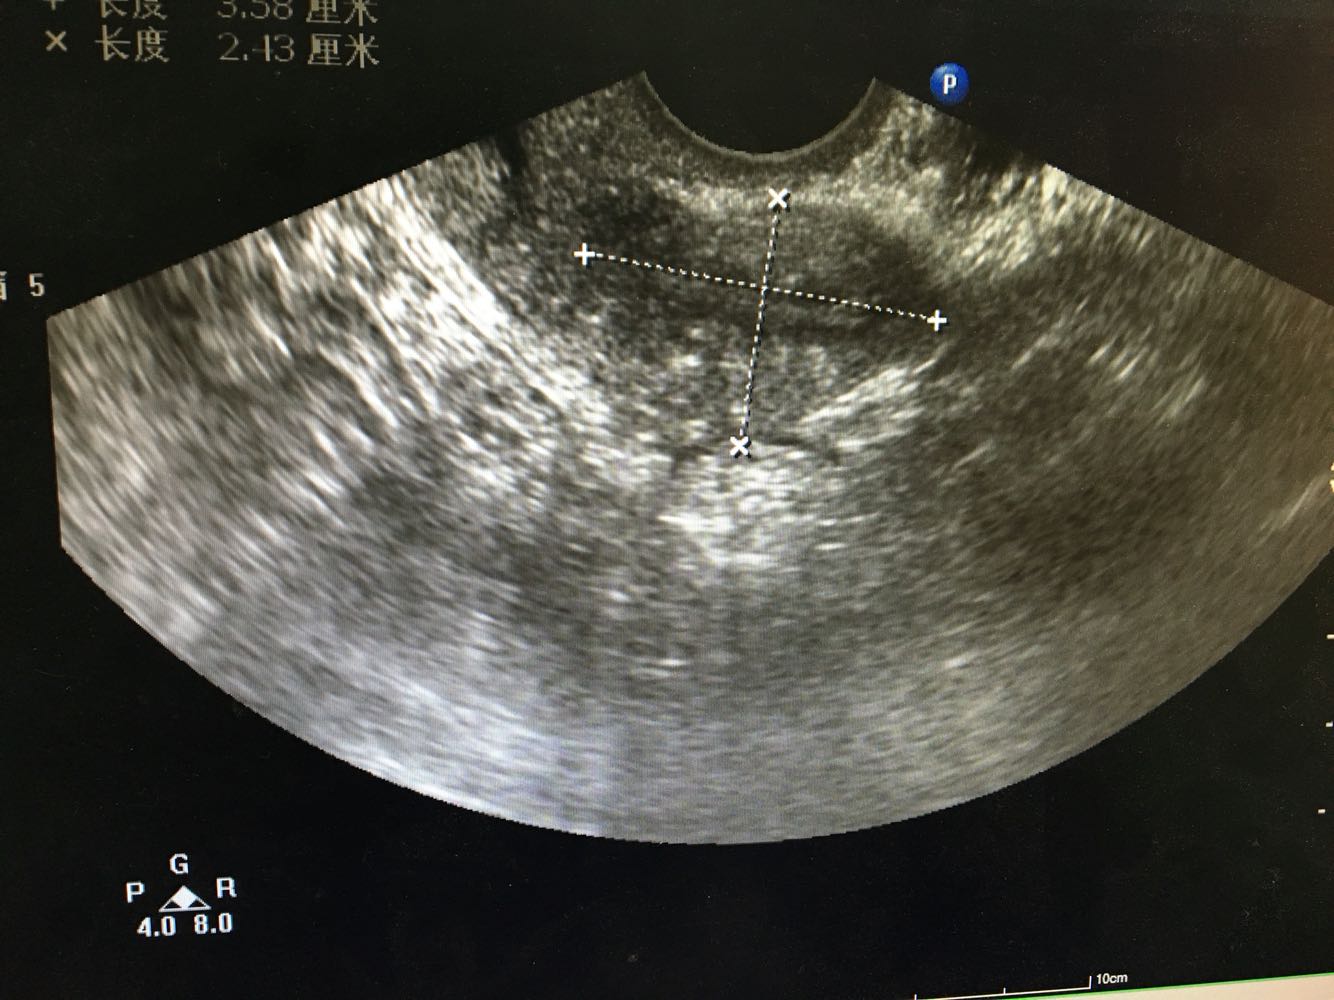

1、患者,女,70岁   2、主诉:发现外阴肿物6月余,进行性加重伴排尿困难2月余  3、现病史:2-0-1-2,18岁 5/25天,经期规则,量中,痛经(-),50岁时绝经。患者于6月前发现阴道口脱出物,当时无腹痛,无尿频尿急,无大便改变,至医院就诊,诊断为子宫脱垂,可还纳,建议提肛等物理治疗,症状未改善。2月前患者自觉阴道口脱出物块感明显 ,有尿频尿急,排尿困难,大便正常,无腹痛。患者未至医院就诊,1月前患者排尿困难进行性加重,伴要不酸痛及下坠感,站立过久及劳累后症状加重,且站立阴道脱出物表面有污秽物,拭去后少量出血。遂至我院就诊,查超声示右附件囊肿,子宫肌瘤。现为求进一步治疗,拟“子宫脱垂II度重”收治入院。患者自患病以来神清,精神佳,胃纳可,夜眠可,有尿频尿急及排尿困难,大便正常,体重无明显变化。

4、妇科检查:外阴:已婚产式阴道:前壁膨出阴道口宫颈:肥大,轻糜 ,突出于阴道口。子宫:萎缩,部分脱出阴道口附件:双侧附件(-)      5、辅助检查: